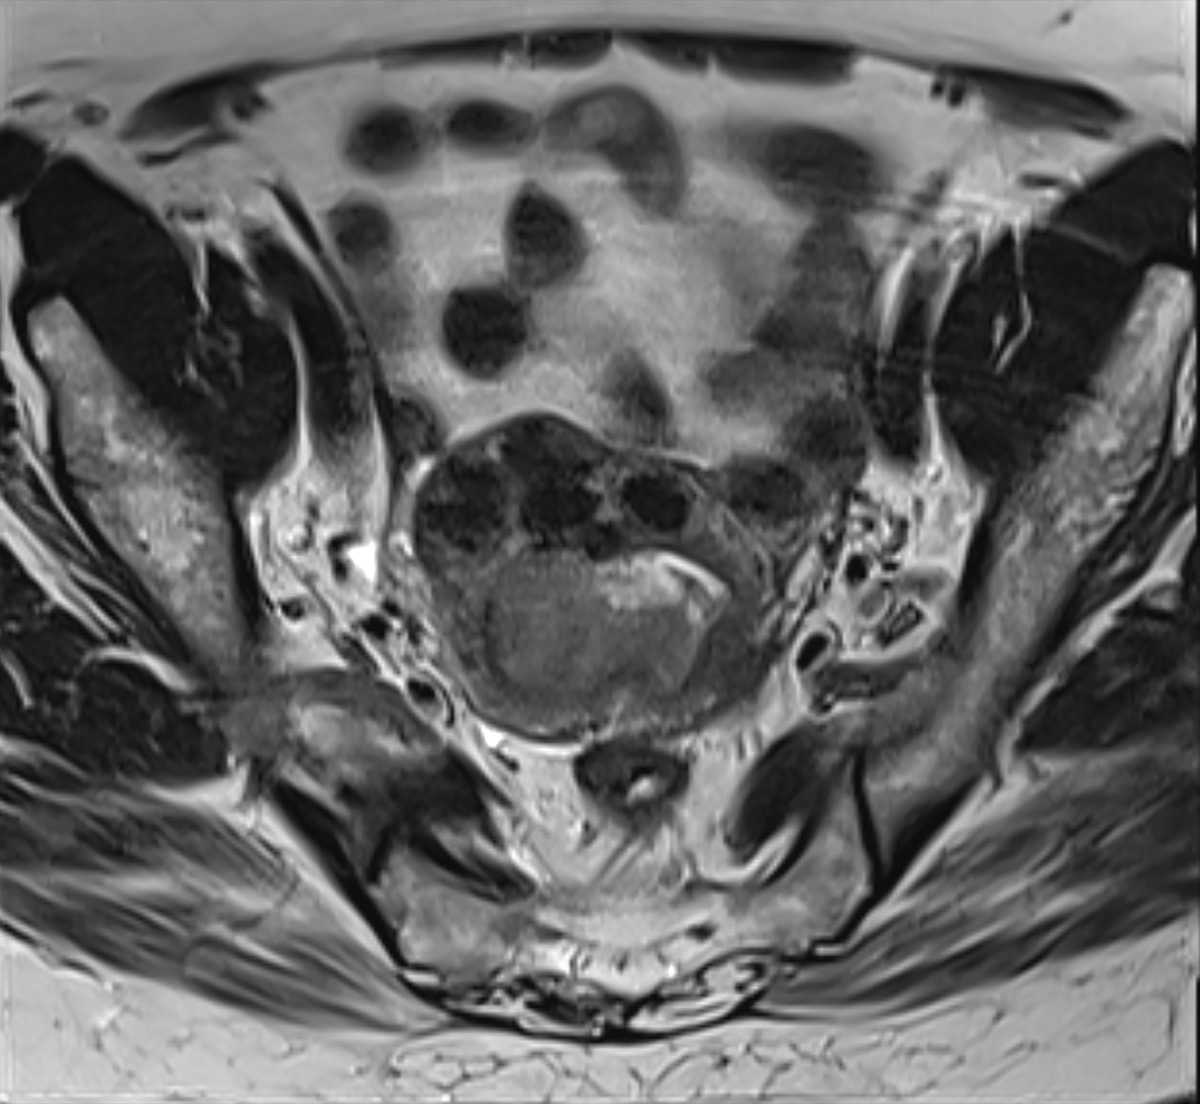

Advancing care through clinical trials

We are spearheading all phases and types of clinical trials, including several sponsored by the NIH, translating novel scientific discoveries into new diagnostics and treatments to help improve clinical outcomes. By enrolling in a clinical trial, you can help our scientists develop new treatments, diagnostic tools and other strategies to prevent, diagnose and treat maternal, fetal, obstetric, gynecologic and women’s health conditions. Through our clinical trials, you may also be able to access emerging technologies and innovative treatments that may otherwise not be available to the general public.

Highlights from our current active clinical trials include: